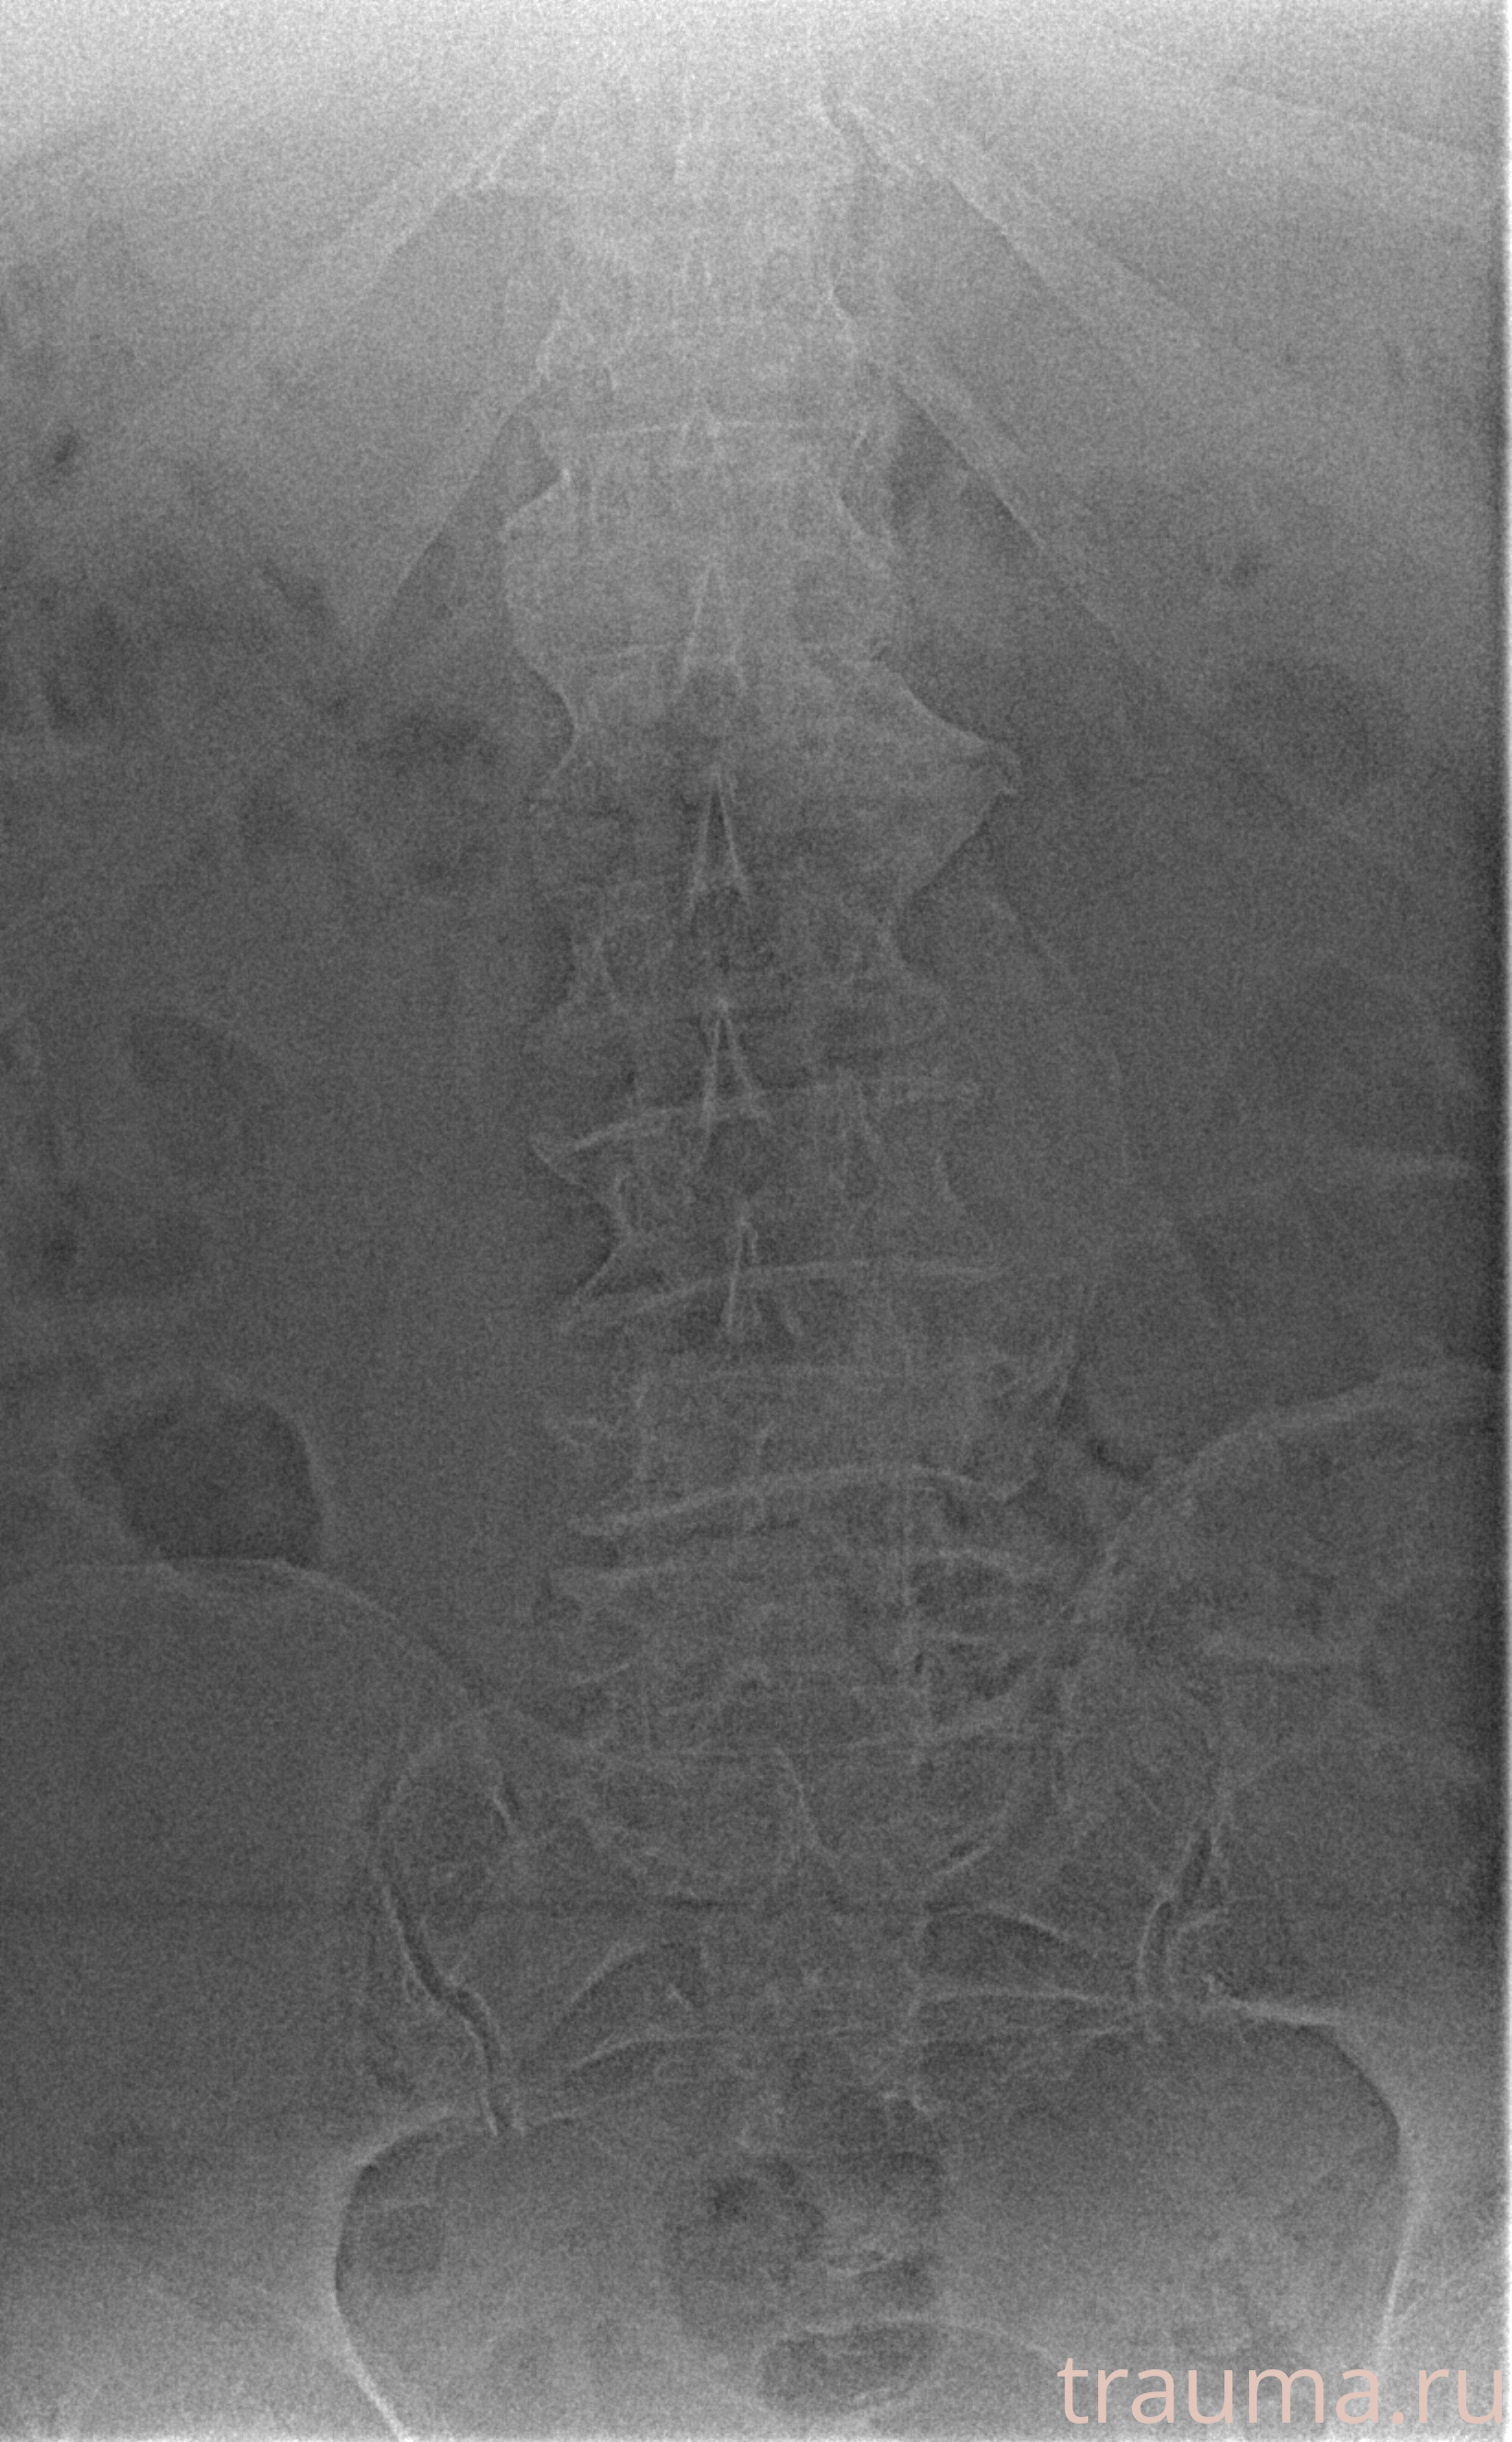

Рентген на дому: по вашему адресу приезжает врач-рентгенолог, травматолог-ортопед с мобильным рентгеновским аппаратом, проводит диагностику травмы или заболевания, делает необходимые рентгенограммы, дает рекомендации по дальнейшему лечению. Получить качественные снимки в домашних условиях возможно благодаря уникальной методике, разработанной МосРентген Центром для института  Склифосовского